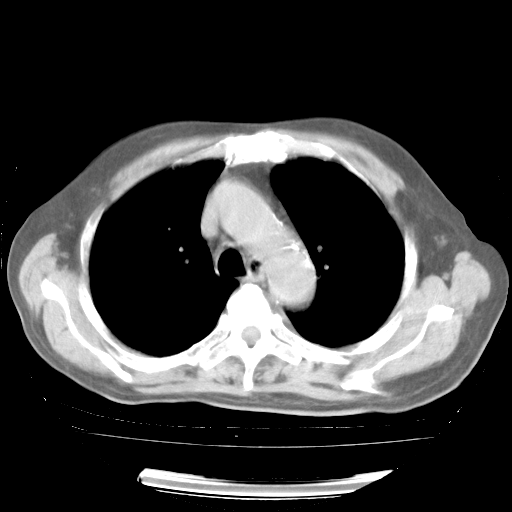

4月28日肺部CT